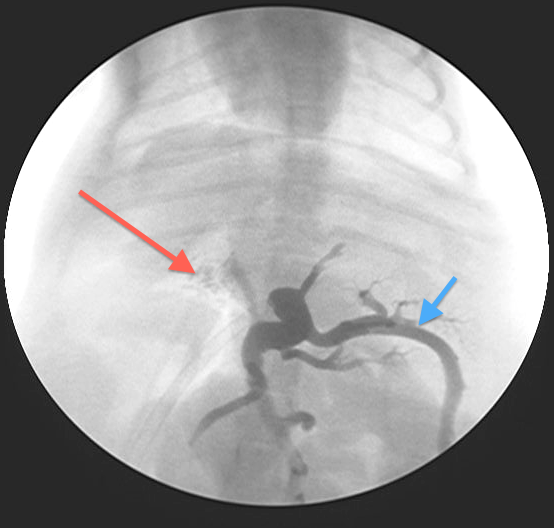

The shunt is identified (Fig 3) and a test ligation performed to confirm identification of the correct vessel and to assess whether or not the patient can tolerate complete ligation of the shunt (Figs 4-5)

Fig 4:

Portovenogram following test ligation (temporary complete occlusion of the PSS) – most contrast has backed up through the splenic vein (blue arrow) with only some contrast going through the right portal vein into the liver (red arrow). This patient would not tolerate complete ligation of the shunt

Most animals cannot tolerate complete ligation at the time of surgery as the portal circulation is usually relatively under-developed and unable to cope with the increased blood flow. This would lead to portal hypertension which can be rapidly fatal.

PSS’s in animals unable to tolerate complete occlusion are therefore gradually attenuated by placement of either an Ameroid Constrictor or Cellophane Band around the shunt allowing gradual reduction of the shunt and simultaneous development of the portal vasculature in response to the increased blood flow.